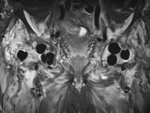

Hip antibiotic beads MRI coronal STIR image

Later coronal STIR MRI image. The beads have low signal and would not be recognizable without radiographic correlation.